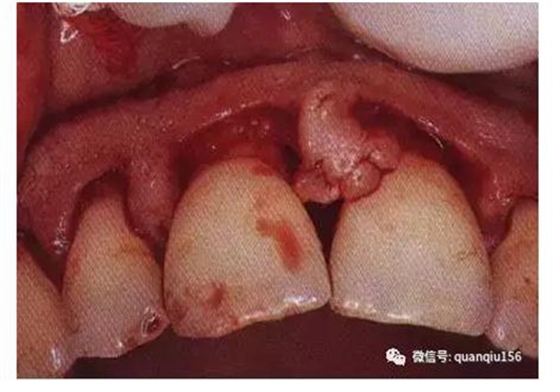

一般在距齦緣1~2mm處進刀,切向根方,直達牙槽嵴頂或其附近。刀片與牙而成10°角左右,以提插方式移動,每次插入均達骨嵴頂。沿著牙的齦緣外形作切口,保留齦乳頭的外形,避免切除齦乳頭,最終形成扇貝形的牙齦外形。切口完成后,袋內壁的上皮和炎癥肉芽組織、結合上皮、袋底與骨嵴頂之間的結締組織纖維與齦瓣分離,仍包繞著牙齒,有待第二切口、第三切口將其徹底清除。

內斜切口是翻瓣術中最關鍵的切口,也是目前采用最多的切口。其優(yōu)點是:將袋內壁的上皮和炎癥組織切除;保留相對完好的袋外側面的角化齦;形成的齦瓣邊緣薄,易于貼附牙面和骨面,愈合后牙齦外形良好。

內切切口與齦緣的距離及切入的角度可隨手術目的而定,并可根據牙齦的厚度、齦瓣復位的位置等情況做適當調整。例如:在做改良Widman翻瓣術或根向復位瓣術時,內斜切口應距齦緣較近,甚至可從齦嵴處切入;而在附著齦較寬的后牙,切口可距離齦緣較遠,以便消除牙周袋;如牙齦較薄,切口應距齦緣較近;如牙齦肥厚增生,切口可遠離齦緣,并增大切入角度,可切除增厚的袋壁組織,形成較薄的符合生理形態(tài)的齦瓣。